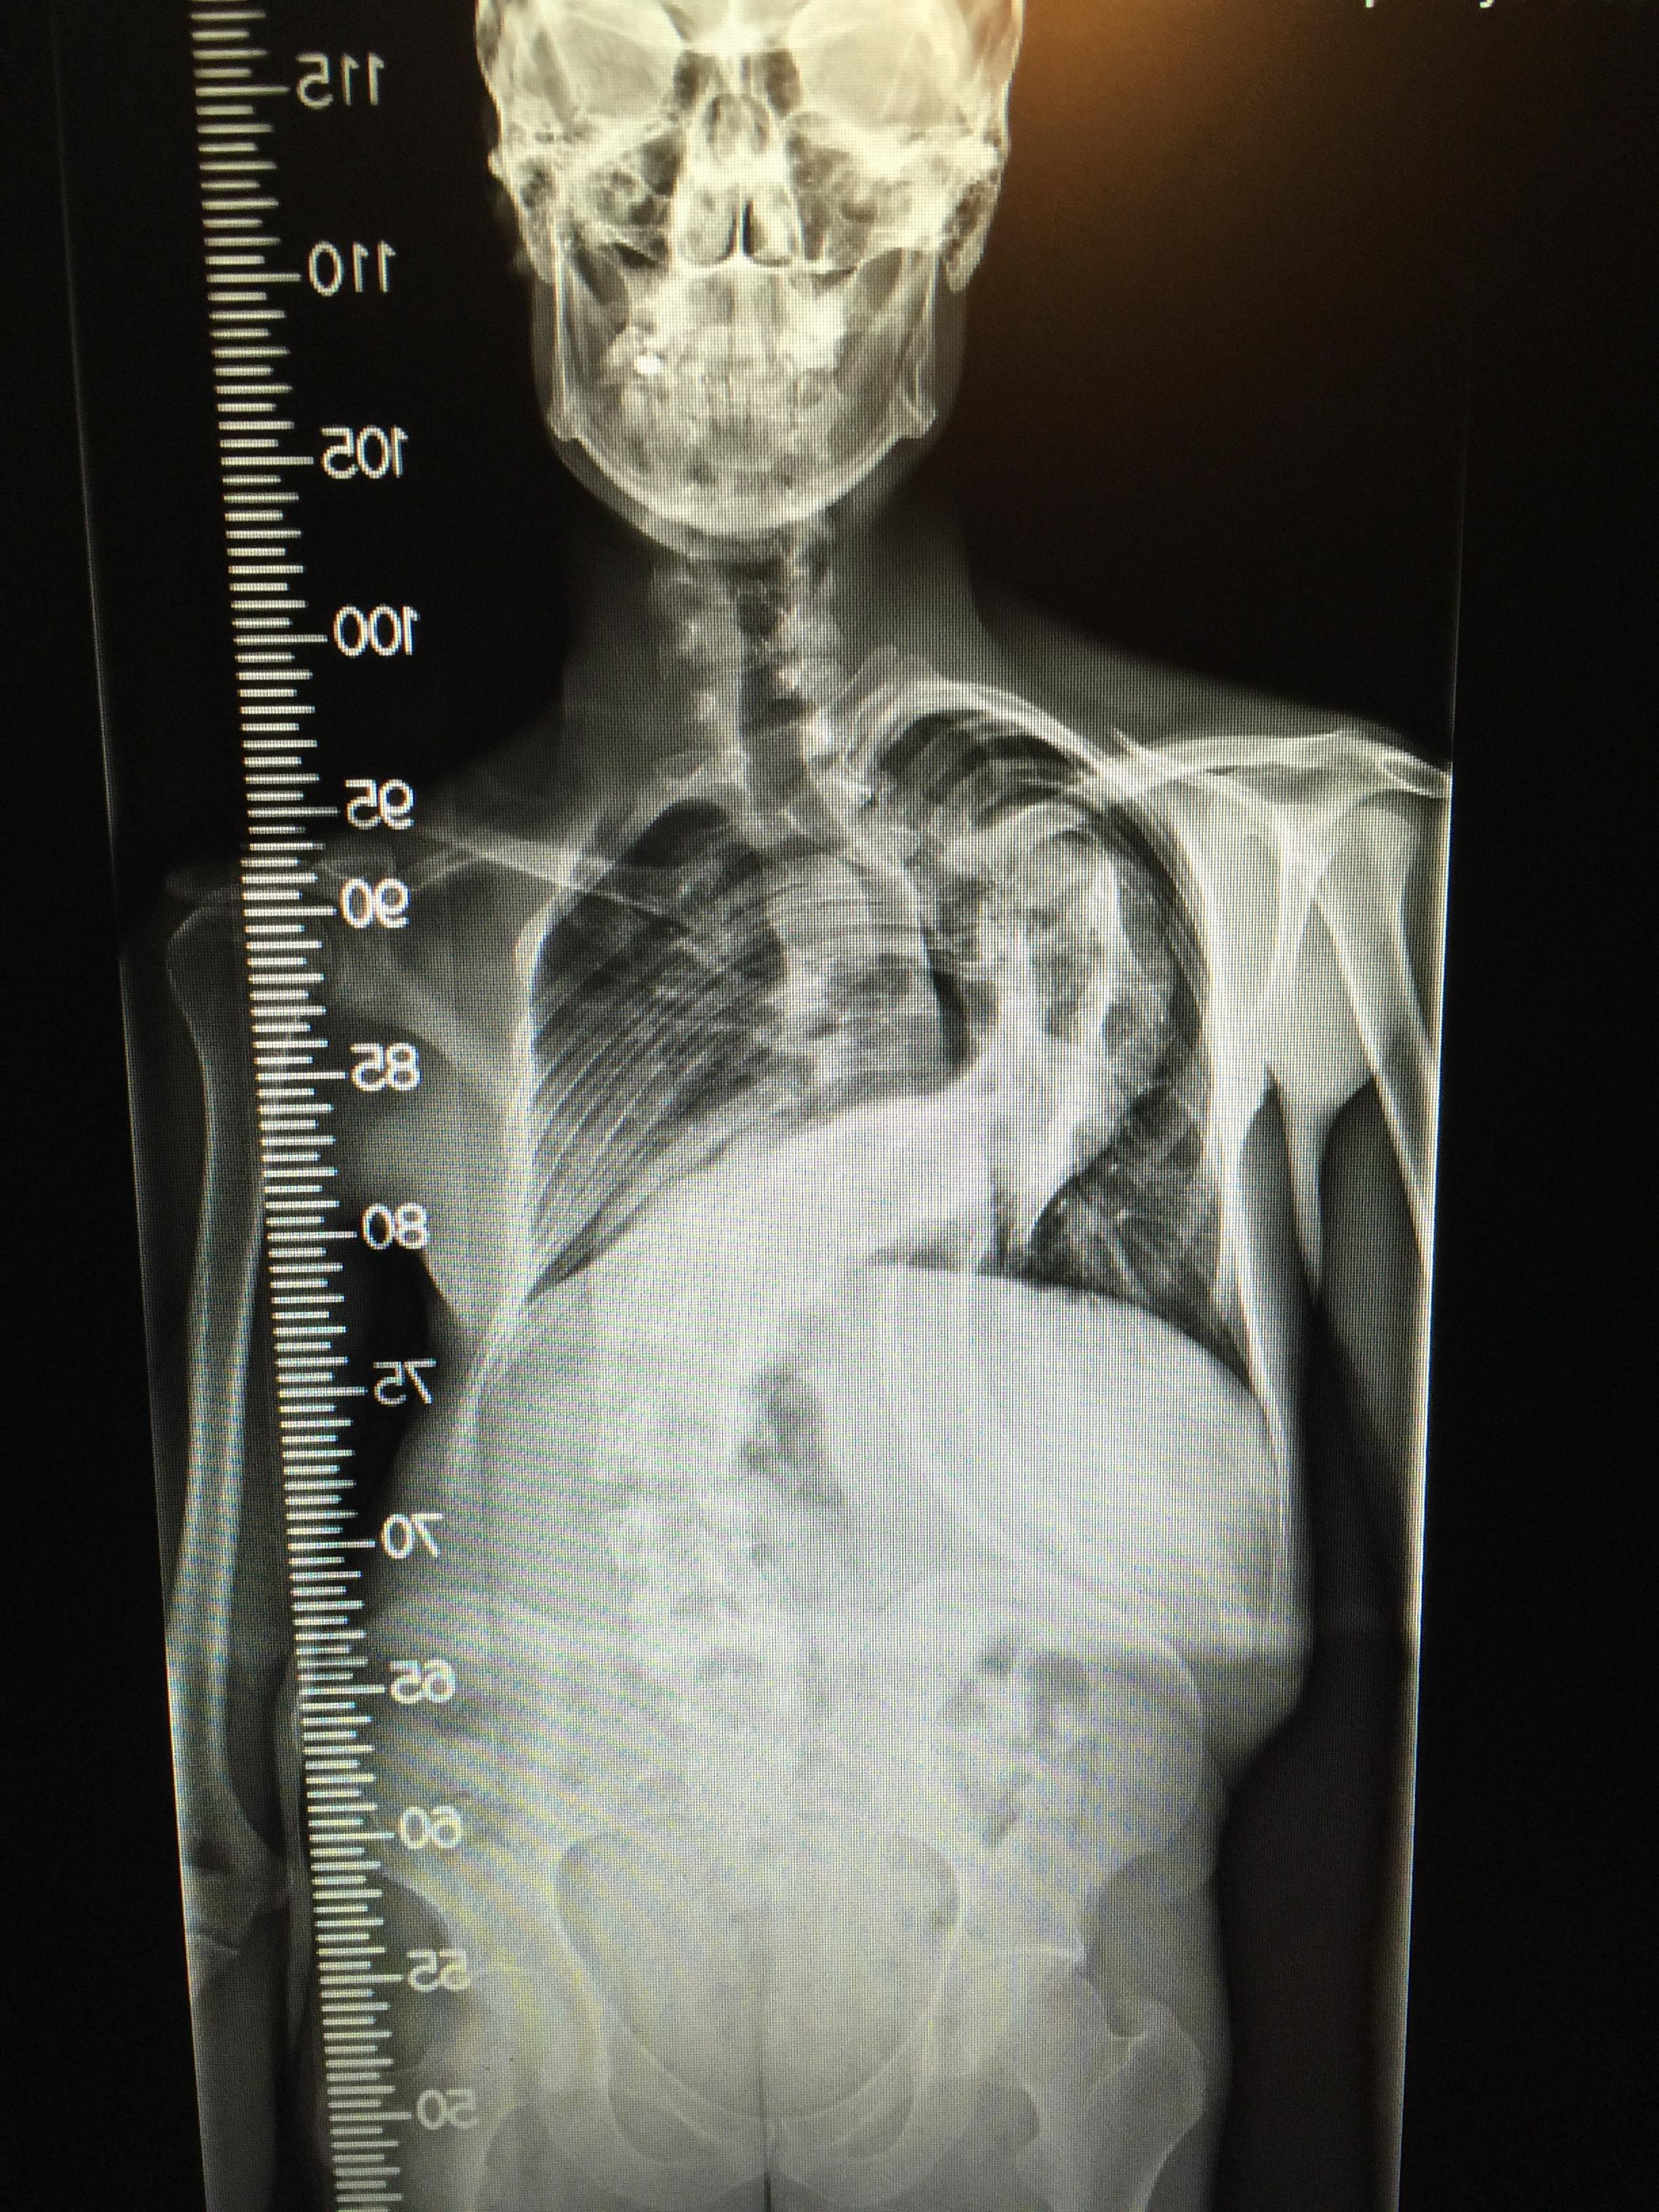

90 degree scoliosis curve r/pics

90 degree scoliosis curve r/pics Girl With Neck At 90 Degrees This article is from jul 24, 2022. The results of the bbc's investigation into strictly come dancing's. Girl with neck bent at 90 degrees treated successfully by doc, for free. An accident, when she was just 10 months old, left her neck bent at 90 degrees. A journey from impossible to possible || story of a brave girl from sindh. Girl With Neck At 90 Degrees.